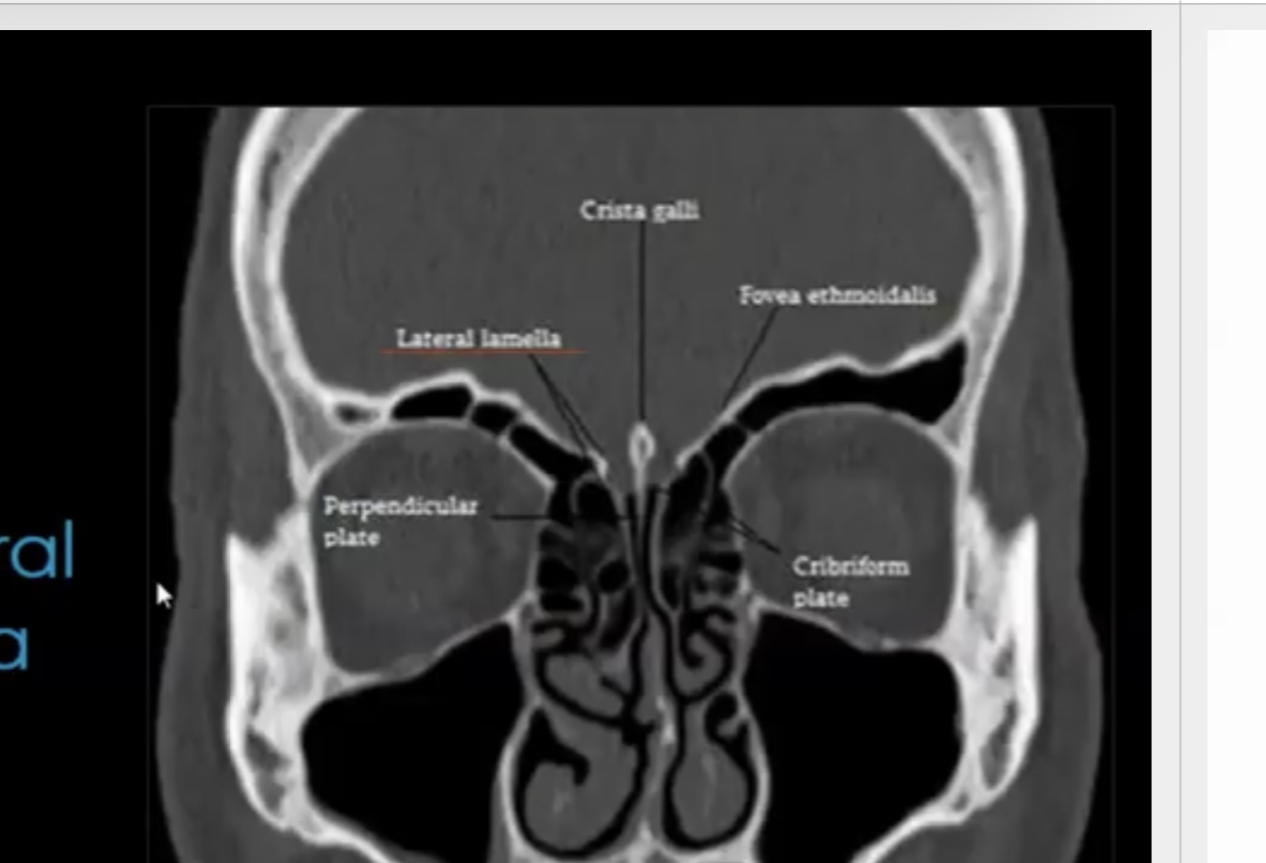

Nme all of the strutures surrounding the Crib. Plate in coronal view?

Keros classification is applied to what?

Whats the maximum grade and its meaning?